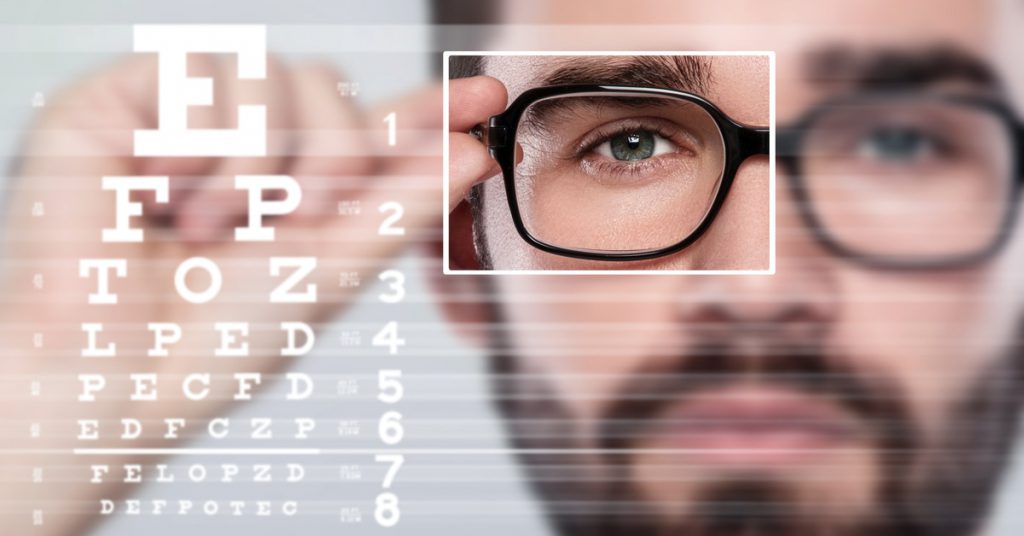

عيوب الإبصار

كثير من الناس يحتاجون إلى نظارات طبية، بسبب مشاكل في الرؤية عندهم. أكثر هذه العيوب انتشاراً قصر النظر و طول النظر.

تسقط الصورة بعد خروجها من العدسة فوق الشبكية تماماً. ولكن عند بعض الناس تسقط أمام الشبكية، فلا يرون الأشياء البعيدة بوضوح . وعلاج حالتهم يكون بوضع عدسات مقعرة تساعد في إسقاط الصور على الشبكية تماماً. نسمي هذا العيب بـ قصر النظر . وعلى العكس منهم، أصحاب طول النظر تسقط الصورة عندهم خلف الشبكية فلا يرون الأشياء القريبه منهم بوضوح فيكون الحل بوضعهم عدسات محدبه تقرب الصورة الى الشبكيه

فحص النظر

لمن يعانون من مشاكل في النظر يجري الطبيب فحصا للنظر بأن يريهم على الحائط حروف ويجرب وضع عدسات مختلفة ليقرر العدسه والنظارة الملائمة